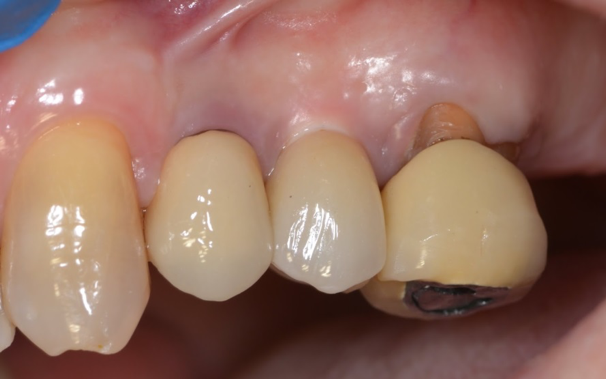

After the preparations were evaluated and accepted by the clinician, provisionals were completed with traditional crown-and-bridge techniques. Then the provisionals were fabricated with a replication stent derived from the diagnostic wax up (Figure 14). The provisionals were well-fitted to both the natural dentition and the ceramic dental implants (Figure 15). The provisional that was fixed to the implant was kept out of occlusion and had a narrow buccal-lingual occlusal table. The smaller occlusal table and short occlusal scheme provided light loading forces and stimulated the bone tissuethe brain detects the stimuli and sends osteoblasts to the area to increase bone density surrounding the implant. The recommendation for the light-loading provisional phase was to have the patient function with the provisionals for 4 weeks.

Fig 15. Provisionals 12 weeks postoperatively.

Figure 15

Fig 16. Final restorations (15 weeks postoperatively).

Figure 16